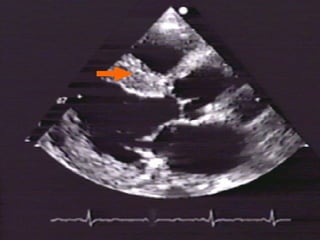

ESTUDIOS DIAGNÓSTICOS: ECG PA Tórax M.A.P.A. Ecocardiograma

CASO CLÍNICO: Femenina de 78 años con edema agudo pulmonar y PA 170/120 mmHg, FC 120 por minuto, S3 apical, estertores crepitantes. ECG: Eje -30o., Voltaje QRS aumentado en derivaciones V5-V6. RX: Cardiomegalia III/IV y HVCP III/IV ECO: Trastorno de relajación y FE 42%

DIAGNÓSTICO: HAS E-2 primaria, riesgo C por cifras y daño a órgano blanco (Cardiopatía hipertensiva) Insuficiencia Cardiaca por Disfunción mixta: Sistólica y Diastólica,  Clase IV NYHA,  Tres Criterios mayores de Framingham

ESTUDIOS DIAGNÓSTICOS: ECGPA Tórax M.A.P.A. Ecocardiograma

CASO CLÍNICO: Femeninade 78 años con edema agudo pulmonar y PA 170/120 mmHg, FC 120 por minuto, S3 apical, estertores crepitantes. ECG: Eje -30o., Voltaje QRS aumentado en derivaciones V5-V6. RX: Cardiomegalia III/IV y HVCP III/IV ECO: Trastorno de relajación y FE 42%

DIAGNÓSTICO: HAS E-2primaria, riesgo C por cifras y daño a órgano blanco (Cardiopatía hipertensiva) Insuficiencia Cardiaca por Disfunción mixta: Sistólica y Diastólica, Clase IV NYHA, Tres Criterios mayores de Framingham